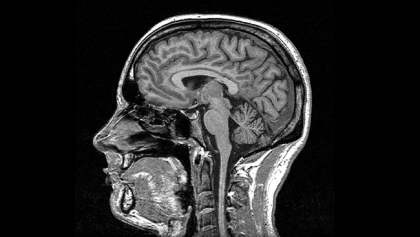

Produits de contraste pour scanner et IRM

Multi-G a développé la première gamme de produits de contraste pour scanner et IRM génériques.

Nous mettons ainsi à disposition des centres d'imagerie médicale en Afrique des produits de qualité à moindre coût, répondant ainsi au besoin croissant de diagnostic avancé pour un meilleure prise en charge des patients et des traitements plus efficaces. Dans un contexte où le patient a souvent la charge complète du coût du traitement, les produits de contraste Multi-G rendent les les soins accessibles à un plus grand nombre, et permettent aux centres d'imagerie de développer leur patientèle.